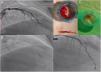

Right coronary artery (RCA) angiography was then performed, and proximal thrombotic occlusion of this artery was also observed (Figure 2A). Successive new aspirations were performed, complemented by balloon angioplasty (Figure 2B). During the procedure, new thrombotic material was formed and therefore IV tirofiban and additional IV heparin was administered. Intracoronary administration of nitrates and adenosine was also required due to no reflow (Figure 2C). Given the high thrombotic load, coronary patency and the high contrast dose already given, the immediate outcome was considered acceptable (Figure 2D) and a new coronary angiography was scheduled. The patient was admitted to the intensive care unit pain-free and clinically stable in Killip class I.

The second coronary angiography, performed after approximately 48 hours, presented a good result from the previous angioplasty of the LAD (Figure 3A) and diffuse disease and distal dissection of the RCA (Figure 3B). We decided to perform RCA angioplasty, initially with balloon, followed by sequential implantation of three Resolute Onyx drug-eluting stents (2.5 mm×38 mm, 3 mm×38 mm and 3.5 mm×38 mm) (Figure 3C), obtaining a good final result (Figure 3D).

Second angiography and angioplasty on day 2 of hospitalization: (A) left coronary artery confirming good outcome; (B) right coronary angiography showing diffuse right coronary artery disease from the proximal segment to the crux, with distal dissection; (C) implantation of the last stent, 3.5 mm×38 mm Resolute Onyx; (D) final result of the second right coronary angioplasty.